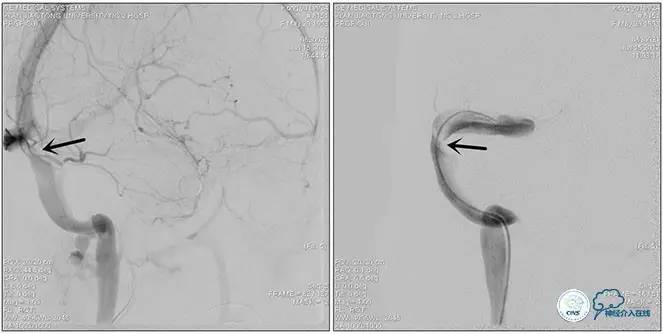

术中右侧ICA造影

右侧ICA斜位及窦内造影

右侧ICA斜位

窦内造影及路图

术中测压:

远端:520mmH2O,

近端:190mmH2O。

治疗方案:

1、8mm×40mm , EverCross球囊扩张;

2、8mm×40mm,Protégé自膨支架成形术。